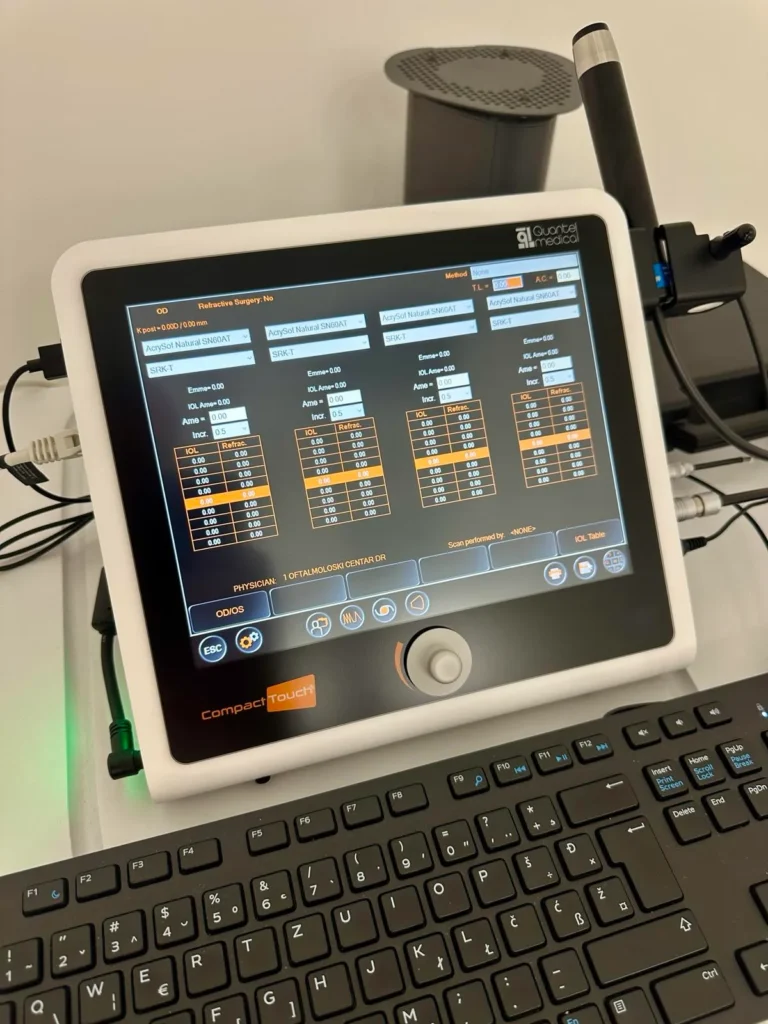

Korišćenje odgovarajuće sonde ultrazvučnog aparata moguće je uraditi kontaknu biometriju kojom se, uz prethodnu primjenu anestetika, mjeri dužina očne jabučice, debljina i zakrivljenost rožnjače i dubina prednje komore oka. Na osnovu tih podataka, biometar obavlja detaljno izračunavanje potrebnog intraokularnog sočiva za operaciju katarakte prema različitim formulama i konstantama.

Naš OCT aparat najnovije generacije pruža mogućnost bezkontaktne OCT biometrije koja pruža kompletan set biometrijskih parametara: aksijalna dužina (AL), centralna debljina rožnjače (CCT), dubina prednje komore (ACD), debljina sočiva (LT), odnos bijelog do bijelog (WTW), zjenica (P).

Biometar pomoću laserskih zraka omogućava bezbolno, precizno mjerenje dužine očne jabučice . Primjenom ove tehnike nije neophodno anesteziranje prednje površine oka i prislanjanje sonde ultrazvuka na oko. Podaci dobijeni ovom metodom često su i precizniji u odnosu na ultrazvučno mjerenje, iako utrazvučna biometrija ostaje sigurniji metod kod uznapredovale zrele katarakte, gdje laser često ne može da “probije” put i napravi ispravna mjerenja.

Sa ponosom ističemo da Oftalmološki Centar Dr Raonić posjeduje uređaj IOLMaster 700. Biometrijski instrument proizvođača ZEISS, zasnovan na SWEPT Source OCT tehnologiji, koji mjeri ključne parametre oka neophodne za ugradnju intraokularnih sočiva (IOL). Uređaj pruža tačne i ponovljive podatke o aksijalnoj dužini, debljini rožnjače (uključujući prednju i zadnju površinu putem Total Keratometry (TK®), dubini prednje komore i debljini sočiva, a sve to bez direktnog kontakta.